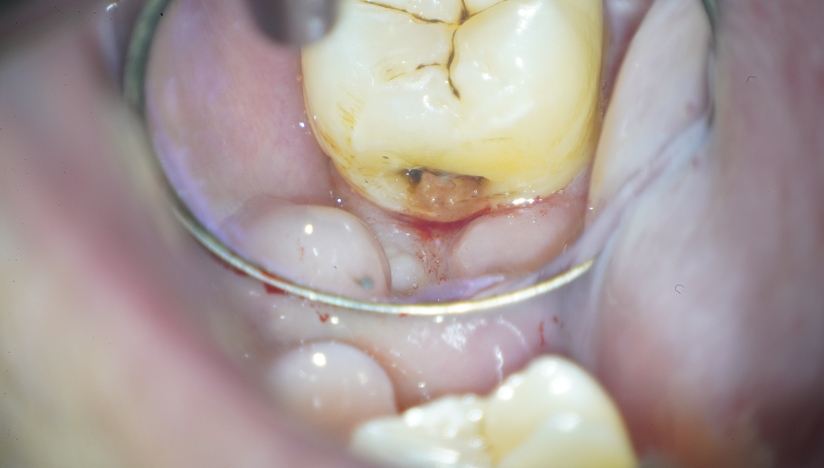

MIを意識しながら予防的拡大を行い

虫歯治療を完了させた症例

Before

After

主訴

虫歯の治療をしたい。

治療内容

セラミックアンレー2本

セラミックインレー1本

IDS(Immadiate Dentin Sealing)3本

治療期間

通院回数2回

治療費用

390,500

治療の

リスク

術後に一時的な知覚過敏症状が出る可能性があります。